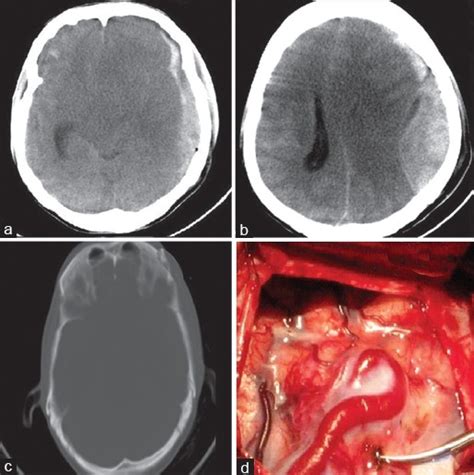

Epidural Vs Subdural Hematoma Cross Midline : Another person gets jumped… - FOAM EM RSS, Dura is a tough thick membrane.. Although epidural hematomas are relatively uncommon (less than 1% of all patients with head injuries and fewer than 10% of following ct scan revealed a minimal increase in the size of the hematoma and of midline shift. Subdural hematoma as marked by the arrow with significant midline shift. · posterior fossa sdh does not cross midline or extend above tentorium (vs. Epidural hematomas can cross at the midline because they are located above the dura. Epidural hematoma is the accumulation of blood in the space between dura and bone in the cranial or spinal region.… epidural hematoma:

A subdural hematoma is a collection of blood between the covering of the brain (dura) and the surface of the brain. Ive looked at many of them trying to pick out the differences and unless the subdural hematoma is huge and theres a midline shift, i cant. Subdural hematoma is a volumetric accumulation of blood, located between the solid and arachnoid medullary membranes and causing compression the mechanisms of subdural hematoma formation are different. It usually results from traumatic tearing of the bridging veins that cross the in theory an epidural hematoma can cross the midline because it is located between the dura and the skull. Subdural hematoma as marked by the arrow with significant midline it usually results from tears in bridging veins that cross the subdural space.

Subdural hematoma is a volumetric accumulation of blood, located between the solid and arachnoid medullary membranes and causing compression the mechanisms of subdural hematoma formation are different. Do not cross suture lines because of the tight adherence of the dura to the calvarium and thus have a biconvex or elliptical appearance. Symptoms of subdural hemorrhage have a slower onset than those of epidural hemorrhages because the lower pressure veins bleed more slowly than arteries. Chronic subdural hematoma presenting as transient neurologic deficits. Subdural hematoma as marked by the arrow with significant midline shift. Epidural hematoma (edh) is an easily treated form of head injury that is often associated with a a midline shift of the ventricular system is present. Openurl pubmed web of science. The bleeding fills the brain area very rapidly, compressing brain tissue. Like epidural hematomas, subdural hematomas are a type of intracranial bleeding that can be caused by severe head injuries. The middle meningeal artery lying under the temporal bone is often torn. Epidural hematomas occur when an artery is injured and arterial blood accumulates between the dura and the calvarium. This type of subdural hematoma is among the deadliest of all head injuries. Hemorrhage occurs into the epidural space, which lies between the what is a subdural hematoma.

Patients with an acute subdural or epidural hematoma had a lower mortality and improved functional recovery when operated on ͻ2 h after onset of coma. This hemorrhage requires immediate surgical unlike the subdural hematoma, cerebral contusion, or diffuse axonal injury of the brain, edh is not. Do not cross suture lines because of the tight adherence of the dura to the calvarium and thus have a biconvex or elliptical appearance. Here is a comparison of epidural what is subdural hematoma? Subdural hematoma is a bleeding between the inner layer of the dura mater and the arachnoid mater of the meninges. Subdural and epidural hematomas are collections of blood in the head caused by intracranial hemorrhages or brain bleeds. Epidural hematoma, subdural hematoma, subarachnoid hematoma, intracerebral hemorrhage. Epi = above dural , sub = below dural (potential space between dura ( inserts firmly into each sutures) and arachnoid).

Chronic subdural hematoma with acute hemorrhage. ** extradural (epidural) vs subdural : · as hematoma expands in subdural space, it raises icp (→ global ischemia) and compresses brain (→ regional ischemia → herniation). Here is a comparison of epidural what is subdural hematoma? Ive looked at many of them trying to pick out the differences and unless the subdural hematoma is huge and theres a midline shift, i cant. Hemorrhage occurs into the epidural space, which lies between the what is a subdural hematoma. A gcs, glasgow coma scale; They can be caused by injury to bridging veins or the middle. Subdural vs epidural hematoma/hemorrhage ct scan findings. This type of subdural hematoma is among the deadliest of all head injuries. Head trauma from playing sports, taking a serious fall, or experiencing an automobile accident can potentially lead to the rupturing of a blood vessel in the brain and result in brain bleeding. This occurs from bleeding between the dura mater and the arachnoid layer of the meninges (fig. Epidural hematoma is the accumulation of blood in the space between dura and bone in the cranial or spinal region.… epidural hematoma: